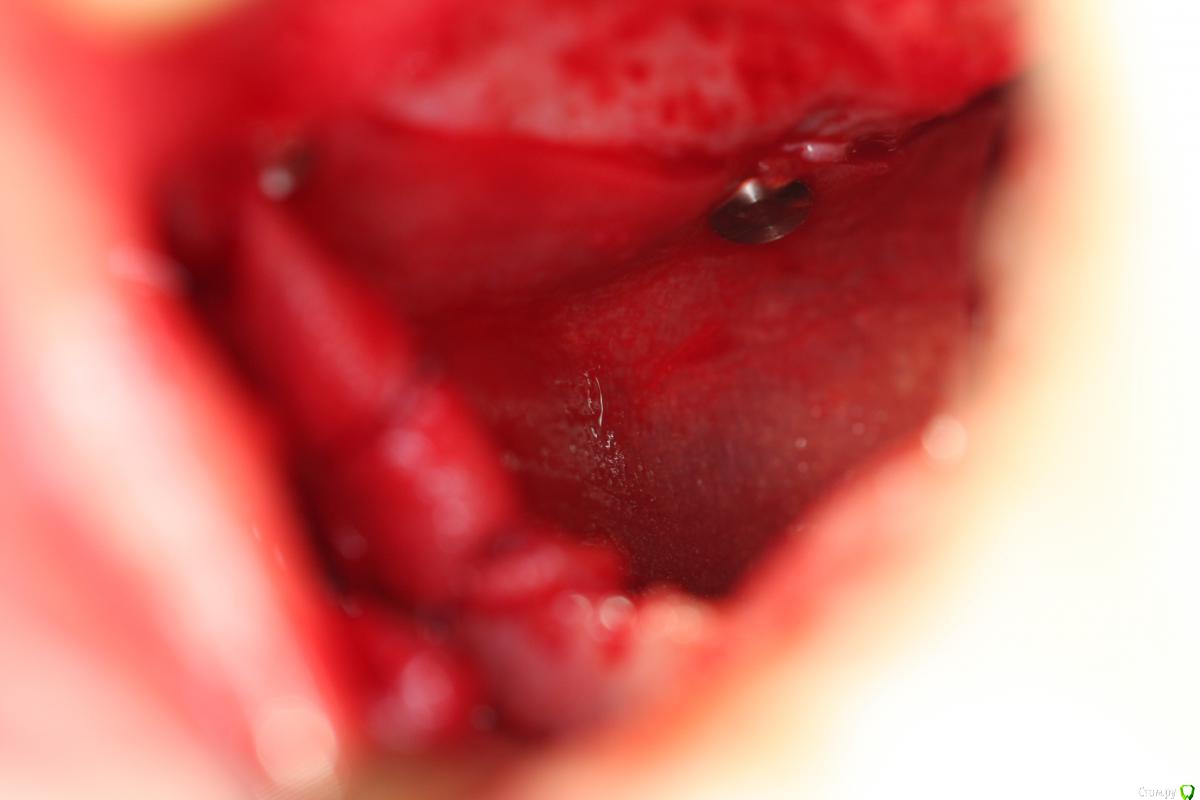

Bier Опубликовано 17 января, 2017 Автор Поделиться Опубликовано 17 января, 2017 7 мес, скорее расслоение, был бы разрыв, все бы в пазуху улетело. Ссылка на комментарий

Bier Опубликовано 17 января, 2017 Автор Поделиться Опубликовано 17 января, 2017 как думаете, почему не весь графт отработал? На установке болтов окно после синуса "окостенелое" было?потому что произошла неполная отслойка слизистой пазухи во время операции. Она подвернулась или расслоилась. 1 Ссылка на комментарий